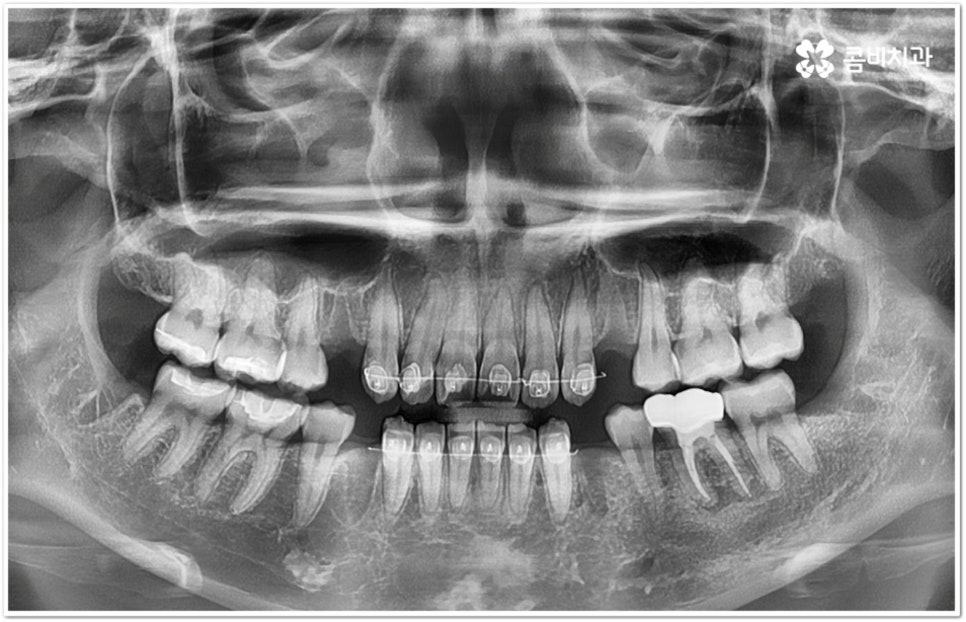

만약 똑바로 자라나고 관리가 용이하며 마주보는 대합치 역시 정상적으로 맹출되었다면 사랑니를 꼭 발치할 필요는 없을 거예요. 그러나 보통 사랑니는 사람의 치아 중에 가장 마지막에 나오는 치아라서 이미 구강 내 공간이 비좁은 상태이기 때문에 비스듬하게 자리를 잡고 일부분만 맹출이 되는 경우가 많이 있어요. 보통 머리가 앞쪽으로 기울어진 근심위로 자리잡는 케이스가 가장 많으며 그 밖에도 치아 머리가 뒤쪽으로 기울어져 있거나 혀쪽, 볼쪽으로 누운 케이스, 아예 옆으로 완전히 누운 케이스 등도 발견되고 있는데요.

잇몸에 반쯤 덮힌 채로 삐뚤게 나온 사랑니는 칫솔질을 제대로 하기 어렵고 위생 관리가 잘 되지 않아 주변 잇몸에 염증이 생기기 쉬우며 어금니까지 충치가 번질 위험이 높아지게 되어 구강 건강 관리 및 예방 차원에서 발치 처치를 해주실 필요가 있어요. 발치 난이도는 사랑니의 경사 각도와 방향 및 치아 뿌리의 길이와 개수, 사랑니 뒤쪽 턱 뼈의 각도 및 형태, 하치조 신경 또는 상악동까지의 거리 등에 따라서 달라질 수 있습니다.

이때 아래사랑니발치 의 경우 아래턱 부근을 지나가는 큰 신경인 하치조 신경을 건드리지 않고 조심스럽게 사랑니만 제거해야 하기 때문에 3D-CT 등 정밀 검진 기계를 통해 사랑니의 매복 위치, 깊이, 각도 등의 상태와 신경까지의 거리 등을 먼저 꼼꼼하게 파악한 후에 발치를 해 줄 필요가 있는데요. 만약 완전히 매복되어 있다면 사랑니 주변에 함치성 낭종이 발생할 수도 있는데 이로 인해 주변 치조골이 파괴되고 어금니 쪽으로 병변이 확산되면 결국 치아를 상실하게 되거나 턱뼈가 약해져서 작은 충격에도 부러지는 현상이 발생할 가능성도 있으므로 될 수 있는대로 치료 시기를 놓치지 않는 것이 중요한 포인트라고 할 수 있어요.

관리하기 까다롭기 때문에 위 아래사랑니발치 를 해 주는 것이 보통이긴 하지만 간혹 사고로 어금니를 상실하거나 유전적으로 어금니가 없으신 분들의 경우 교정 치료를 통해 어금니 대신 사용하는 사례가 있으니 필요하다면 발치 결정 전에 꼼꼼하게 검진을 받아보실 필요가 있어요.

모든 경우에 사랑니가 어금니를 대신할 수는 없으며 사랑니로 어금니를 대체하기 위해서는 사랑니의 상태, 이동 가능 공간, 주변 구조물 및 전체 구강 구조 등 환자분들의 상황을 먼저 면밀하게 살펴본 후 교정 치료 계획을 세심하게 세워 잇몸과 사랑니의 손상 없이 치료할 필요가 있으므로 고난도 과정에 맞게 술자의 높은 숙련도가 요구되는 만큼 노하우가 풍부한 의료진을 선택하시길 권유드리고 있습니다.